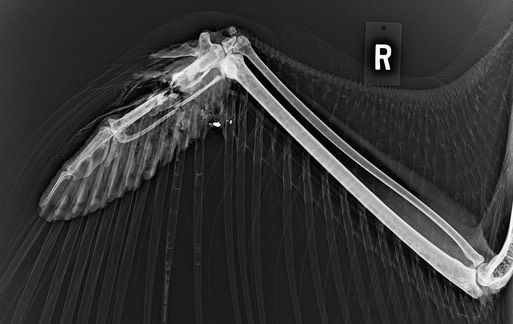

Bald Eagle 22-083

An immature Bald Eagle was found near Enterprise, OR. A radiograph showed the eagle had been shot. The damage was not repairable and the eagle was euthanized.